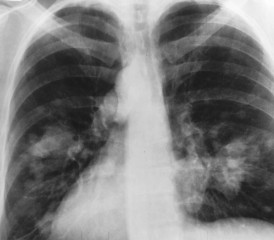

What Does Mesothelioma Look Like on an X-Ray?

Lighter and hazy areas on the X-ray show possible mesothelioma tumors.

On a chest X-ray, pleural or pericardial mesothelioma tumors appear as wispy white areas around the lungs, while calcified tumors appear bright white. Bones appear white and healthy lungs are dark. Most abnormalities appear as lighter areas that are hazy or solid.

Large fluid buildup called pleural effusions, a common mesothelioma symptom, can make an entire lung field look “cloudy” or even completely white on an X-ray. Tumors and scarring may distort chest anatomy. Compressed lungs or a raised diaphragm can be visible on an X-ray.

X-rays are 2D, making it hard to determine if a tumor is in the lung, pleura or the mediastinum around the heart. Additionally, X-rays don’t clearly show peritoneal or testicular mesothelioma. CT, MRI and PET/CT scans offer more detailed images for all mesothelioma types.